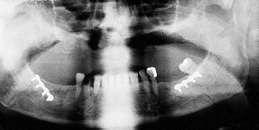

The primary purpose of the consultation is the outpatient follow-up treatment and care of patients who have undergone surgery following bone injuries to the upper and/or lower jaw. In addition to patients with fractures of the facial skull, patients with injuries to the teeth and facial soft tissues are also followed up.

Osteosynthesis procedures are performed at our clinic according to modern international standards. Mini and micro plates made of titanium and special medical steel are used to stabilize the fractured bones. Especially for the treatment of temporomandibular joint fractures a joint plate was developed in our clinic. The development and application of resorbable osteosynthesis materials is at the same time a research task of the clinic.